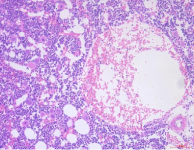

(2)病理验证:骨缺损处组织HE染色,Masson染色,进行联合分析,计算软组织占比,编织骨占比,皮质骨占比,评估新骨形成的质量和成熟度。

HE染色